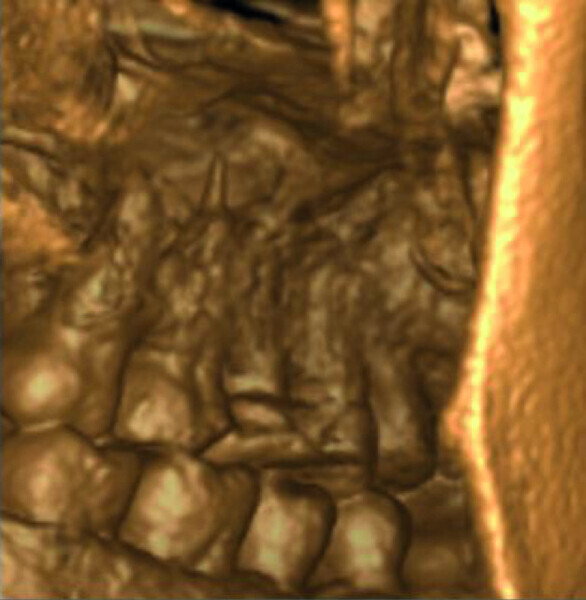

Maxillary sinus and root canal therapy complications